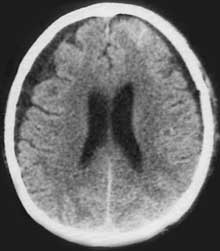

КТ головного мозга. Двусторонние хронические субдуральные гематомы.

Посттравматические хронические субдуральные гематомы - инкапсулированное объемное кровоизлияние, располагающееся под твердой мозговой оболочкой и вызывающее местную и общую компрессию головного мозга.

Хронические субдуральные гематомы отличаются от острых и подострых травматических гематом отграничительной капсулой, возникающей, обычно, через 2 недели после травмы, которая определяющей все особенности их патогенеза

, клинического течения и тактики лечения. Объем ХСГ колеблется от 50 мл до 250 мл и чаще составляет 100-150 мл.

Этличительный клинический признак этих гематом в том, что светлый промежуток может длиться неделями, месяцами и даже годами. Клиническая манифестация исключительно полиморфна. Наблюдается как постепенное развитие компрессионного сидрома, так и внезапное резкое ухудшение состояния больного до сопора и комы спонтанно или под влиянием разных дополнительных факторов (легкая повторная травма головы, перегревание на солнце, употребление алкоголя, простудные заболевания и др.).